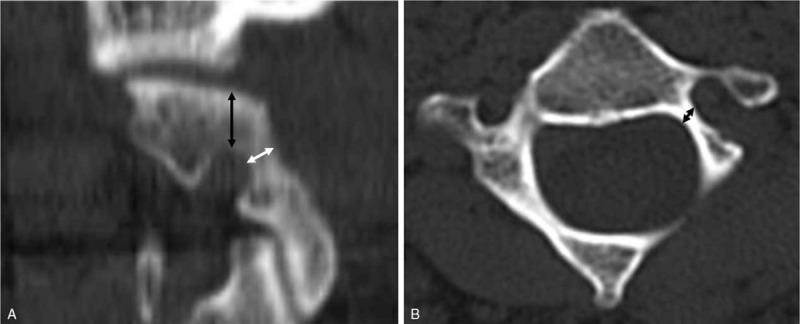

An observational study.To evaluate the safeties of placing three different alternative C2 screws using the freehand technique under high riding vertebral artery (HRVA) and to analyze the C2 morphometry in patients with HRVA.A retrospective analysis of radiologic data was performed on patients that underwent C2 instrumentation from September 2004 to December 2017. Two hundred fifty-one patients were included, and 90 of these patients (35.9%) had a unilateral or bilateral HRVA. We placed three alternative C2 screws including superior pars, inferior pars, and translaminar screws. Computed tomography was used to assess cortical breeches of screw placement and obtain morphometric measurements of C2 pars and lamina, that is, superior pars height/length, inferior pars length, and laminar thickness/length. We used the modification of the all India Institute of Medical Sciences outcome to define cortical breach.In total, 117 alternative C2 screws were inserted in 90 patients; 7 superior pars screws (6%), 69 inferior pars screws (59.0%), and 41 translaminar (35%) screws. Although cortical breaches occurred during 31 screw placements (26.5%), these were unacceptable in only two cases (1.7%). No symptomatic neurovascular complication was observed after screw placement in any case. Mean height of C2 superior pars was 3.8 ± 1.8 mm and mean thickness of C2 lamina was 5.2 ± 1.1 mm. Mean lengths of superior pars, inferior pars, and lamina were 17.8 ± 3.0 mm, 13.6 ± 2.2 mm, and 26.7 ± 3.3 mm, respectively. Superior pars height and lamina thickness < 3.5 mm that was a minimal diameter of cervical screw were 49.6% and 6.8%, alternative C2 screw was not available in these cases.Placements of alternative C2 screws using the freehand technique were achieved accurately and safely in patients with HRVA. However, preoperative morphometric evaluation is essential to determine the best option for C2 instrumentation and C2 screw length to avoid neurovascular complications.

一项观察性研究。旨在评估在高位椎动脉(HRVA)情况下徒手置入三种不同替代C2螺钉的安全性,并分析HRVA患者的C2形态学。对2004年9月至2017年12月期间接受C2器械植入的患者的放射学数据进行回顾性分析。共纳入251例患者,其中90例(35.9%)有单侧或双侧HRVA。我们置入了三种替代C2螺钉,包括上关节突螺钉、下关节突螺钉和椎板螺钉。使用计算机断层扫描评估螺钉置入的皮质骨穿透情况,并获取C2关节突和椎板的形态学测量值,即上关节突高度/长度、下关节突长度和椎板厚度/长度。我们采用全印度医学科学研究所结果的改良版来定义皮质骨穿透。

总共在90例患者中置入了117枚替代C2螺钉;7枚上关节突螺钉(6%)、69枚下关节突螺钉(59.0%)和41枚椎板螺钉(35%)。尽管在31次螺钉置入过程中发生了皮质骨穿透(26.5%),但只有2例(1.7%)是不可接受的。在任何情况下,螺钉置入后均未观察到有症状的神经血管并发症。C2上关节突的平均高度为3.8±1.8mm,C2椎板的平均厚度为5.2±1.1mm。上关节突、下关节突和椎板的平均长度分别为17.8±3.0mm、13.6±2.2mm和26.7±3.3mm。上关节突高度和椎板厚度<3.5mm(这是颈椎螺钉的最小直径)的情况分别为49.6%和6.8%,在这些情况下无法使用替代C2螺钉。